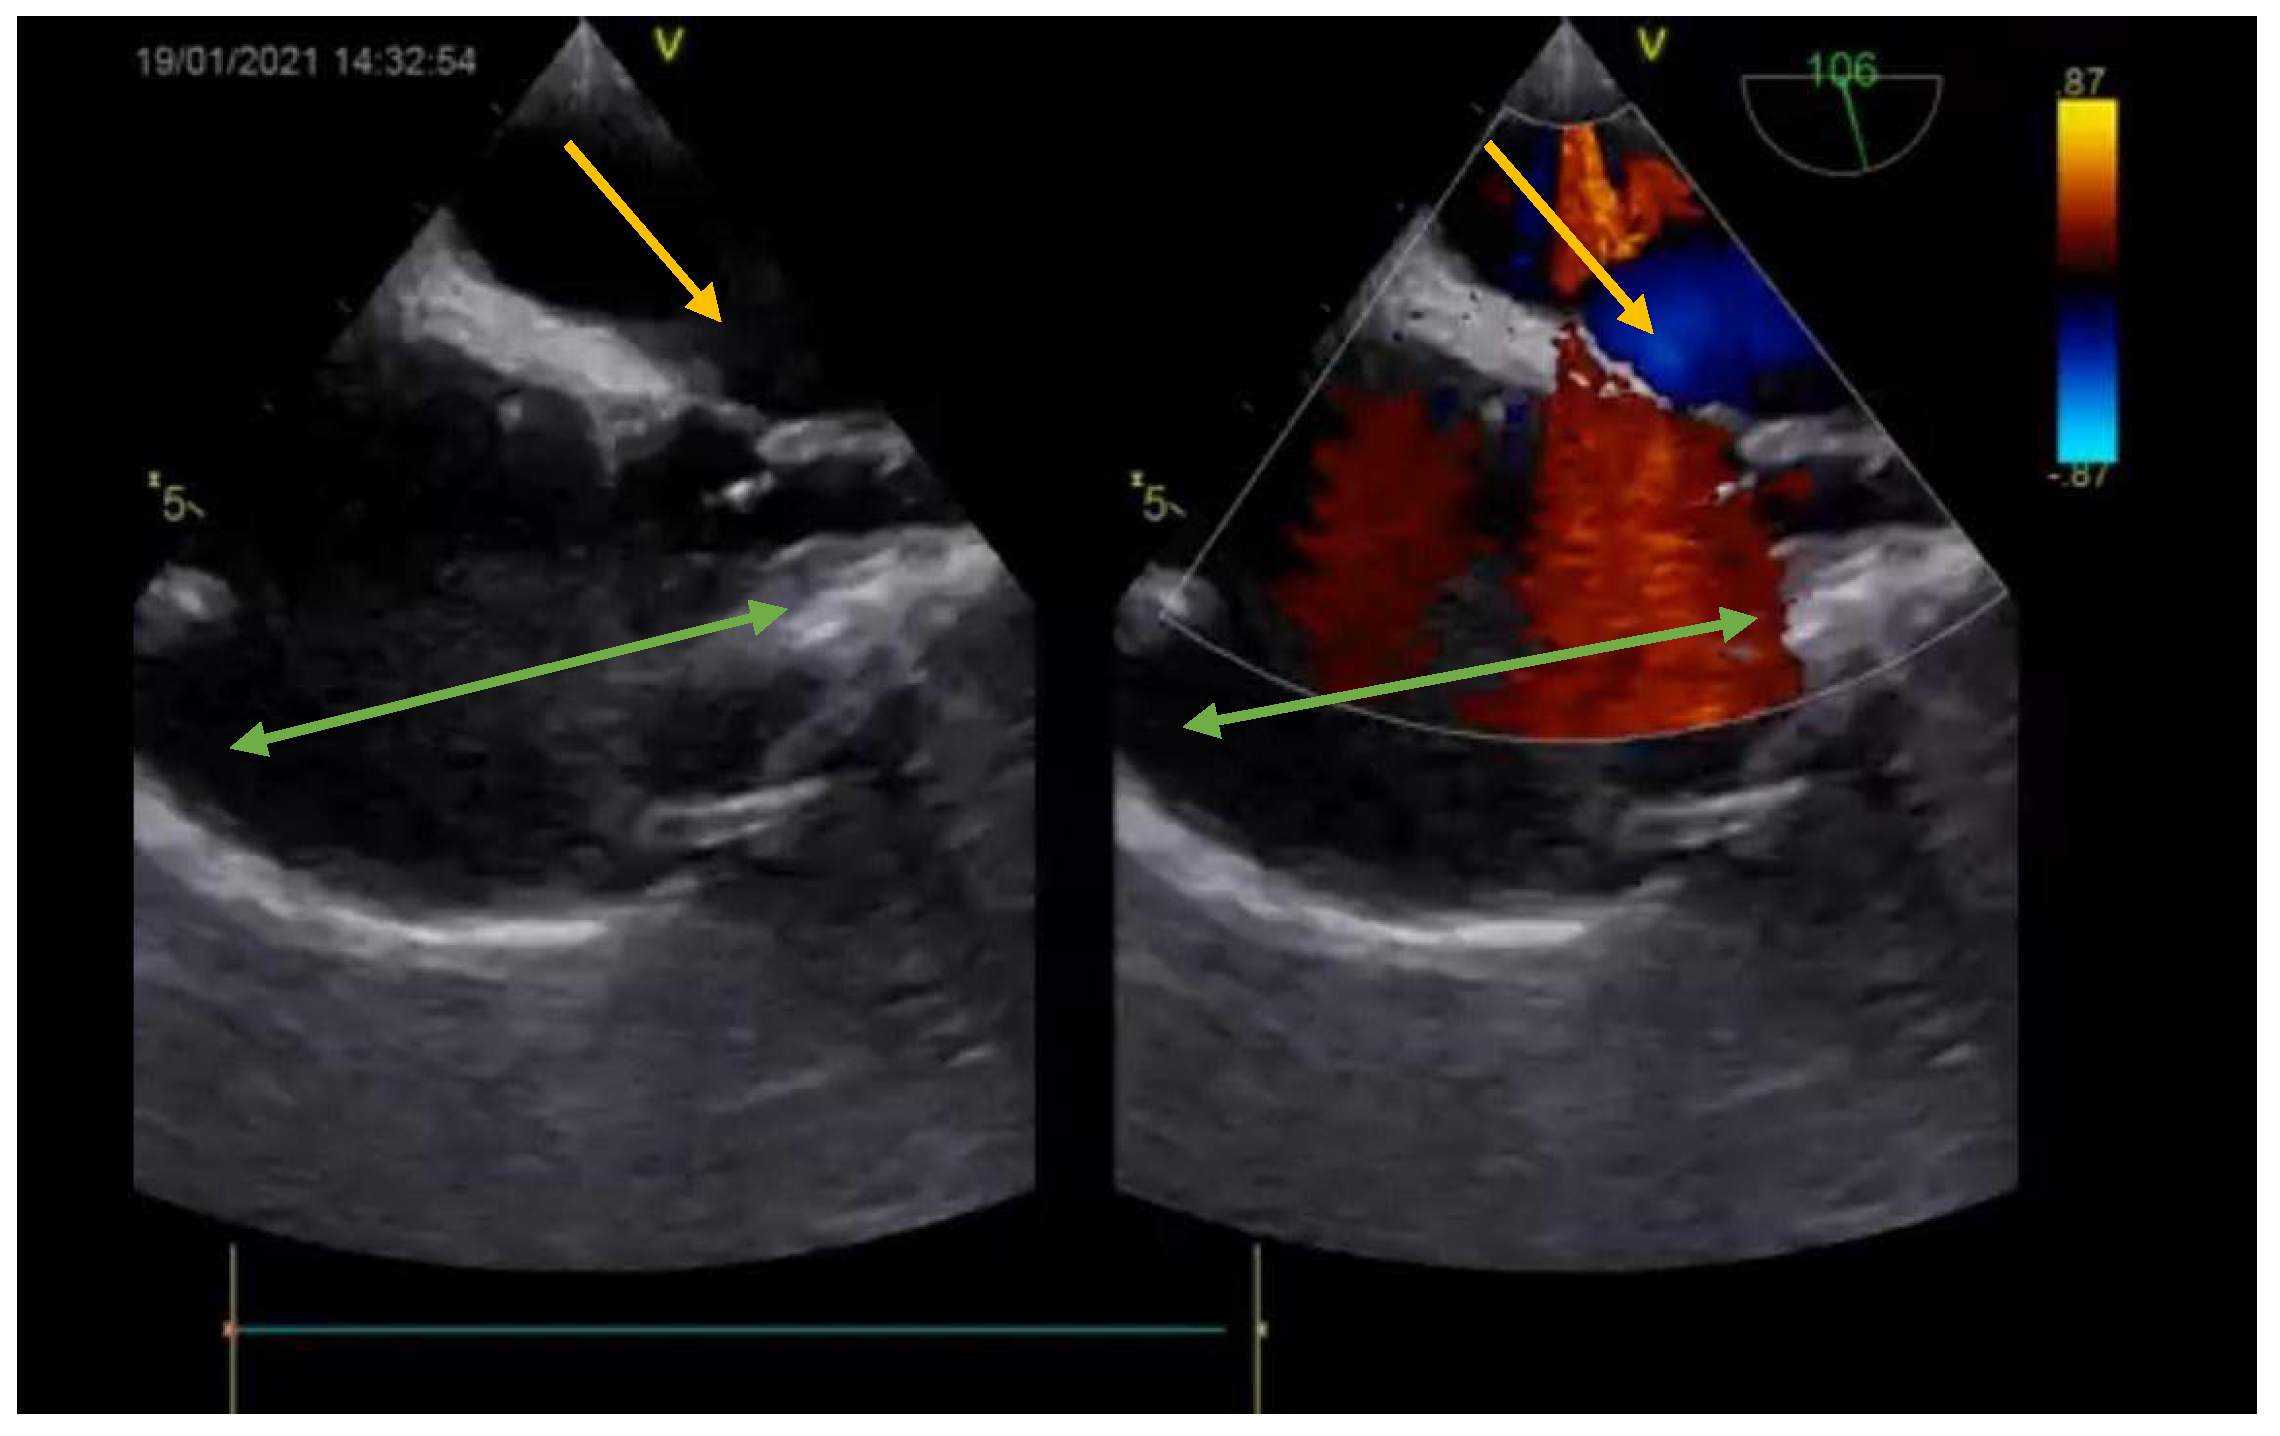

The diagnosis was based on the transthoracic echocardiography (Figure 1 and Figure 2). It revealed an SV-ASD with PAPVD which appeared to open in the right atrium, a dilated right atrium and ventricle, and a left-to-right shunt with Qp:Qs of 2.3 (Qp-pulmonary flow/Qs-systemic flow). The patient had normal pulmonary artery pressure, which was measured during echocardiography.

Figure 1. Preoperative echocardiography (bicaval view—Doppler; SVC—green arrow; right atrium—orange arrow; interatrial septum—white arrow) showing the ASD (yellow arrow).